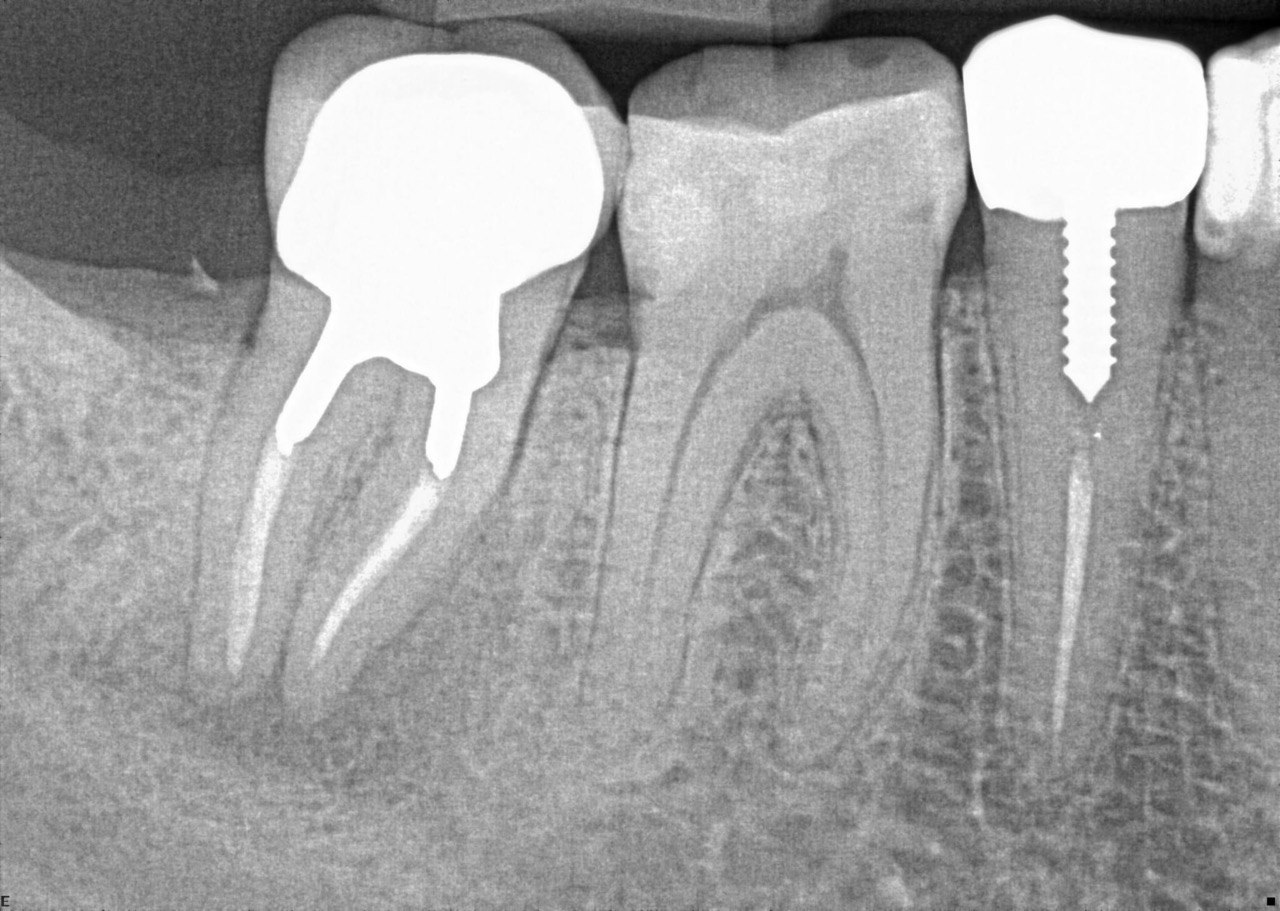

ACJ Quiz - Restorative Dentistry X-Ray 01

Question 1: What materials cannot be seen in the print of the X ray?

Question2: Which surface shows overhang?

Question 3: Which option is not evident on the print of the X ray?

Question 4: Which options cannot be seen in the print of the X ray?

Question 5: What options cannot be selected for tooth # 4.6?

Question 6: What options cannot be seen in the print of the X ray?

Question 7: What option cannot be identified on the print of the X ray?

Question 8: What condition can be seen in the X ray?

Question 9: Which option cannot be seen in the lower jaw?

Question 10: Which option can be selected for the following X ray?